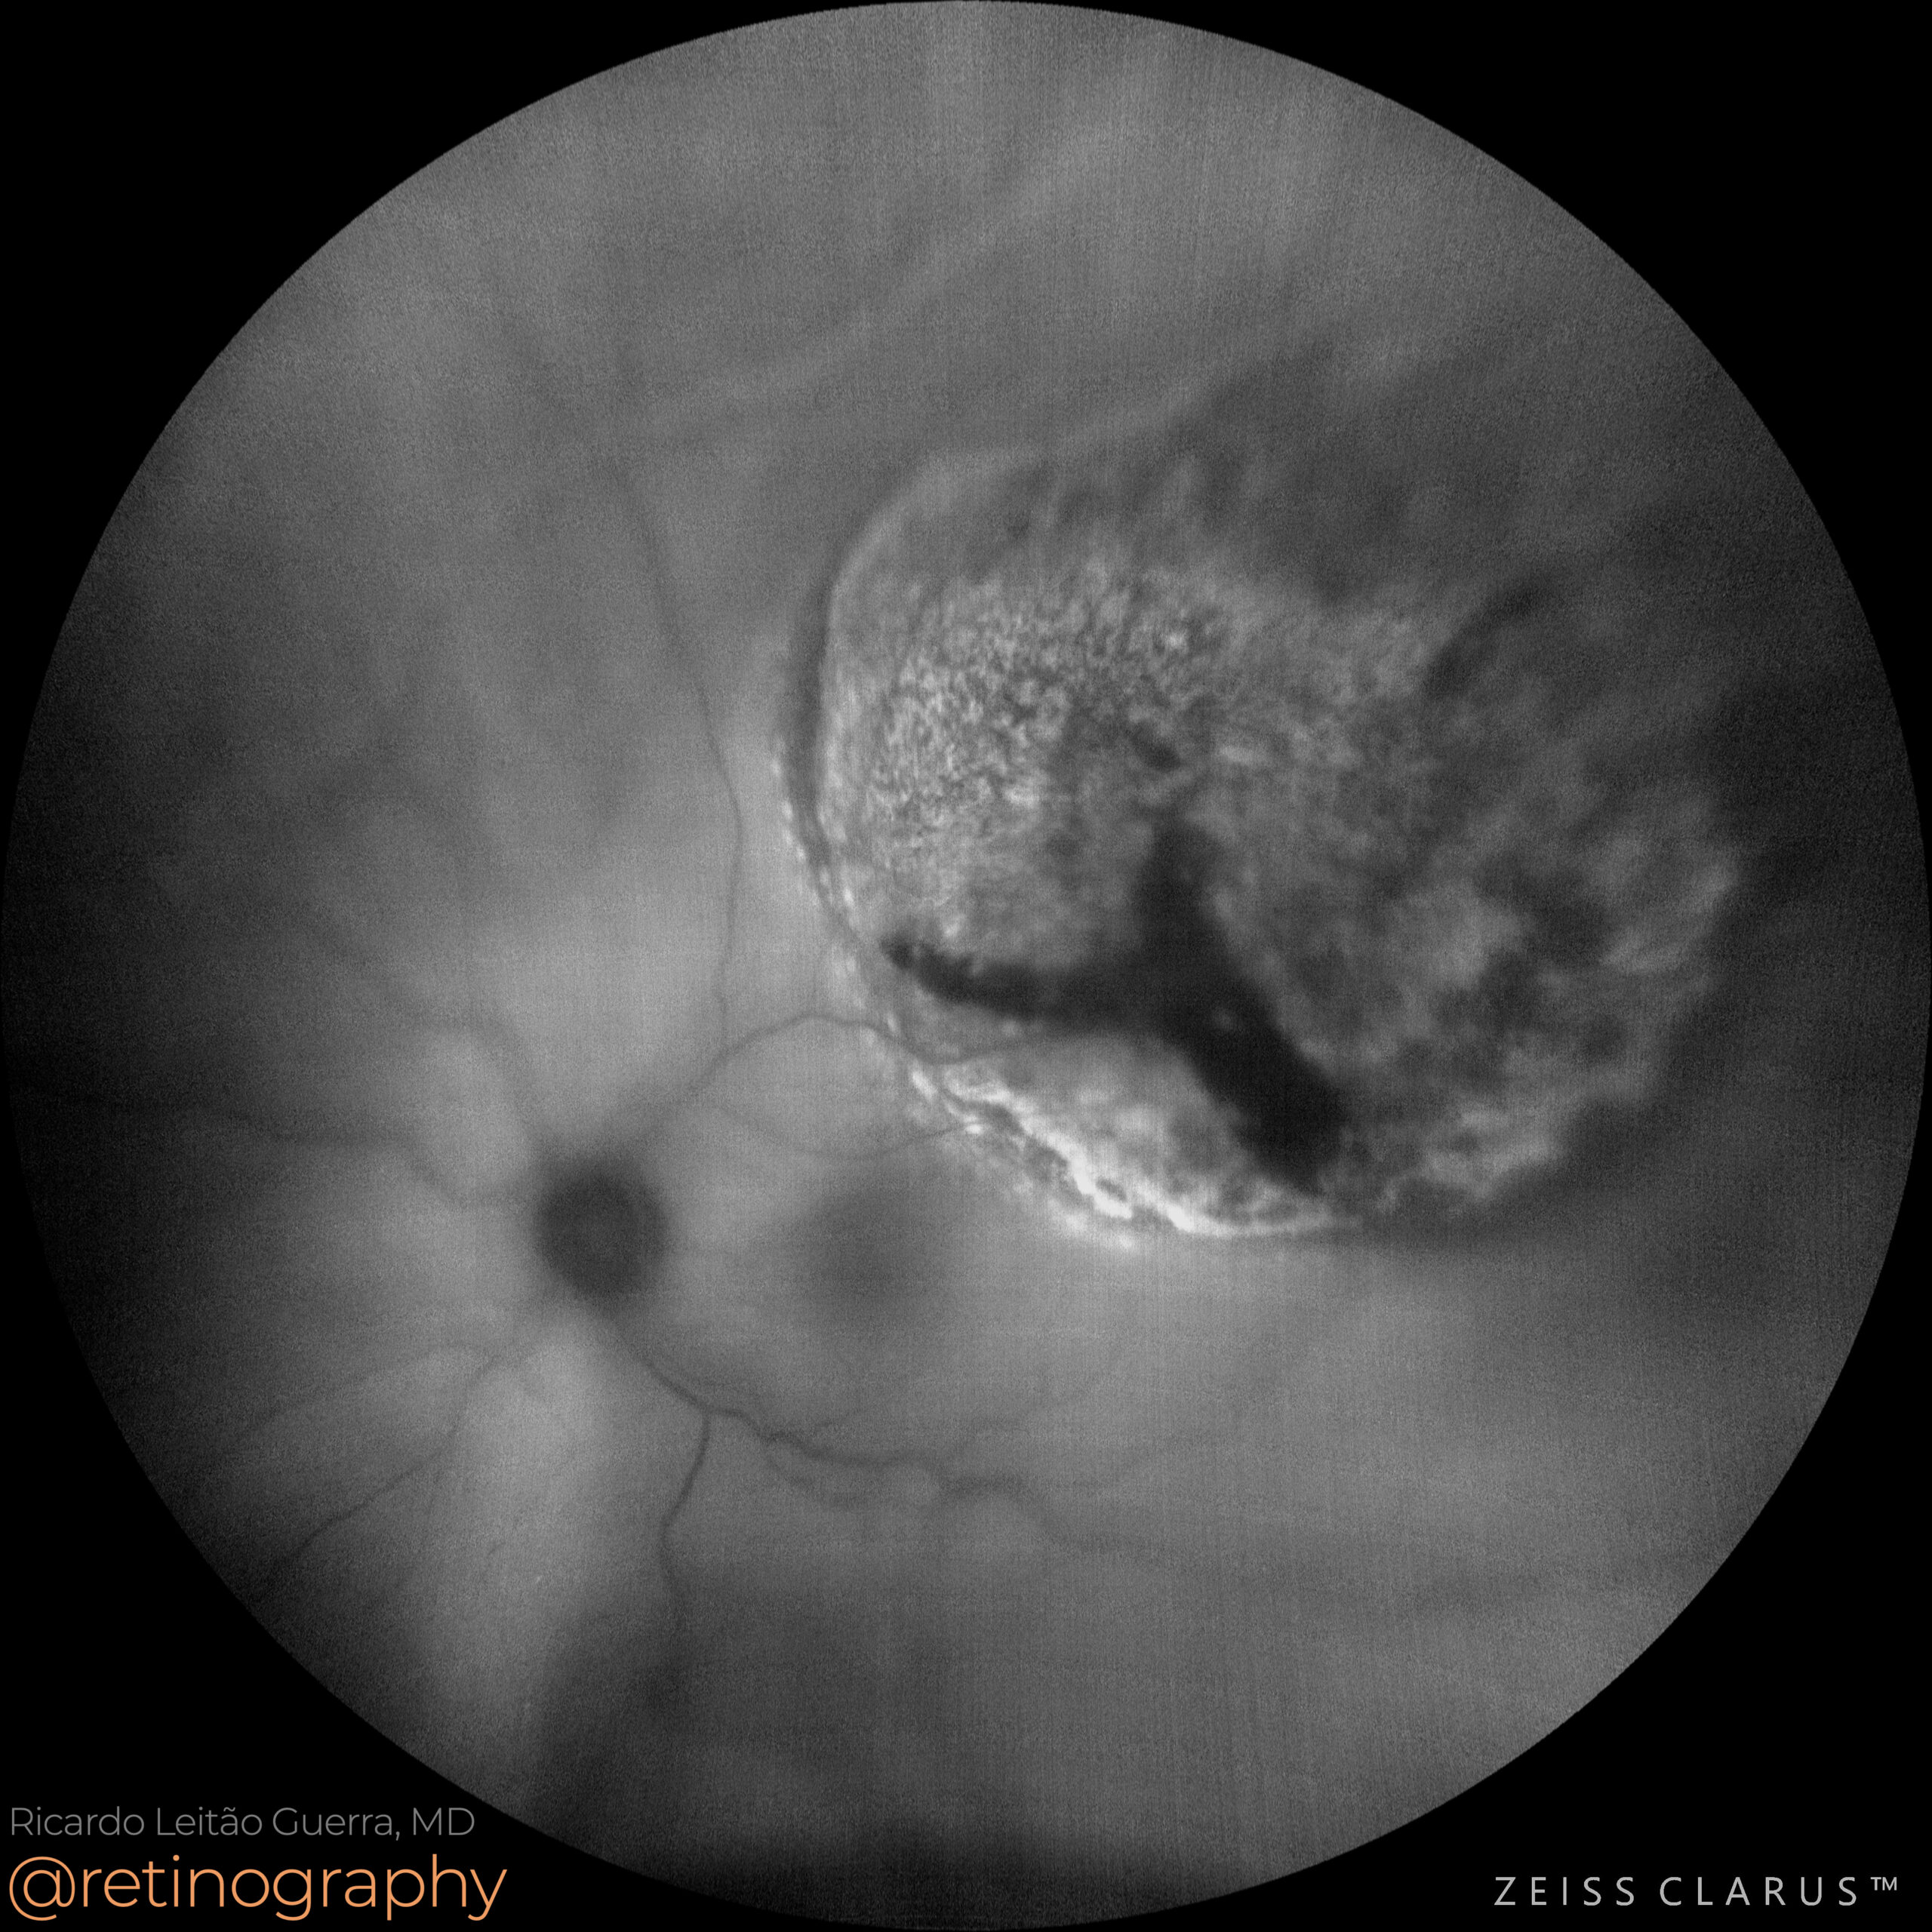

Choroidal melanoma

72yo Choroidal melanoma can cause serous retinal detachment due to fluid leakage from the tumor or associated vascular abnormalities. Fundus examination typically reveals a dome-shaped or mushroom-shaped lesion with overlying retinal elevation. In selected cases, brachytherapy is used to preserve some vision and avoid more invasive, vision-threatening surgical procedures.